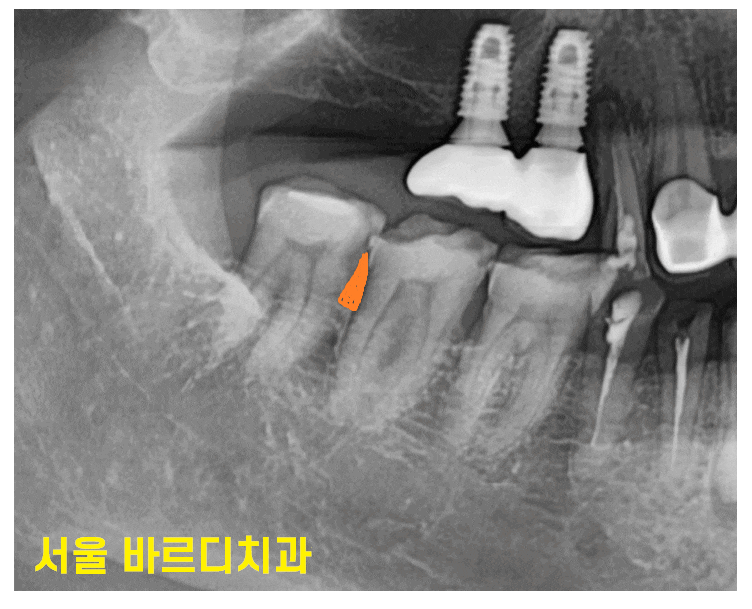

치아는 1개씩 서로 맞물리는 짝궁이 있는데

어느 한쪽이 빠져버리면

맞닿이는 치아가 없겠죠~?

그러다 보면 맞닿이던 방향으로

치아가 움직이게 됩니다.

이런 현상을 "치아 정출"이라 말합니다.

오늘 환자분처럼 위에 치아가 없는 경우 치아 올라옴

아래 치아가 없는 경우 위에 치아 내려감 현상이 생겨요.